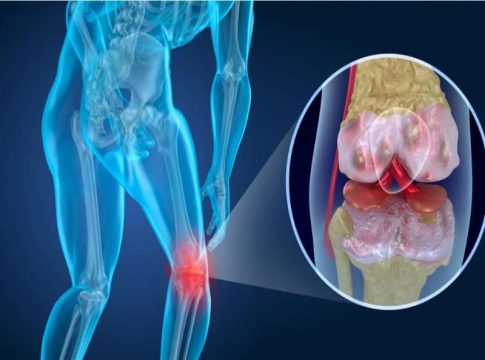

- Artrosis de rodilla

Las articulaciones de las rodillas la conforman el fémur, la tibia y el peroné. Este tipo de artrosis se caracteriza por el deterioro que genera el cartílago, provocando que se genere dolor con la actividad física, problemas para caminar y permanecer de pie. Esta enfermedad aparece en las personas antes de los 50 años de edad.